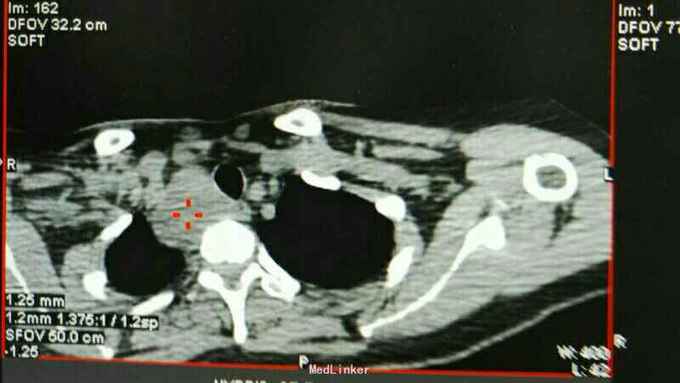

巨大甲状旁腺腺瘤囊性变

高钙危象,血钙4以上,右巨大甲状旁腺瘤囊性变,暴露右无名动脉,右颈动脉,右锁骨下动脉,右颈静脉,右无名静脉,右迷走,喉返起始部,胸膜顶,小心完整切除。6X5x4Cm。